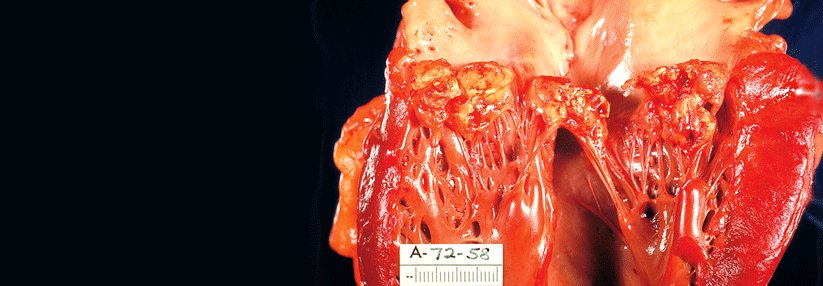

In diesem Fall haben Streptokokken eine Herzklappe befallen. Oft sind auch weitere Strukturen betroffen. In diesem Fall haben Streptokokken eine Herzklappe befallen. Oft sind auch weitere Strukturen betroffen. © Science Photo Library/Christol, D. / CNRI

Die Keime können viele Strukturen am Endokard befallen, vom Klappensegel bis hin zur Schrittmachersonde, kombiniert oder einzeln (s. Kasten). Ungefähr in 70 % der Fälle lässt sich in der Echokardiografie eine Vegetation nachweisen. Wie aber verfährt man bei den 30 %, bei denen sich im Echo nichts findet? Laut einer Studie, in der alle Teilnehmenden eine kontinuierliche Bakteriämie aufwiesen, ändert die negative Bildgebung nichts an der Prognose. „Das heißt, die Echokardiografie alleine sollte nicht dazu dienen, eine Endokarditis ausschließen zu wollen“, sagte Prof. Mangner. Man brauche einen multimodalen Ansatz, der Bildgebung, Mikrobiologie und Klinik beinhaltet.